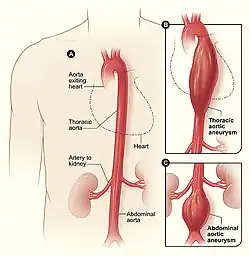

An abdominal aortic aneurysm (AAA) refers to aneurysmal dilation of the aorta confined to the abdominal cavity. Most commonly, aneurysms are asymptomatic and located in the infrarenal position. Often, they are discovered incidentally or on screening exams in patients with risk factors such as a history of smoking. Patients with aneurysms which have a diameter less than 5 cm are at <1% rupture risk per year. When the aneurysm meets size criteria it can be treated with aortic replacement or EVAR.

- Thoracic

Thoracic aortic aneurysms are contained in the chest. Aneurysms of the descending aorta can often be treated with thoracic endovascular aortic repair or TEVAR. Treating aneurysms which involve the ascending aorta are generally within the scope of cardiac surgeons, but upcoming endovascular technology may allow for a more minimally invasive approach in some patients.

Abdominal aortic aneurysms can be classified as infrarenal, juxtarenal, pararenal or suprarenal as depicted in the illustration.

Abdominal aortic aneurysms can be classified as infrarenal, juxtarenal, pararenal or suprarenal as depicted in the illustration. -